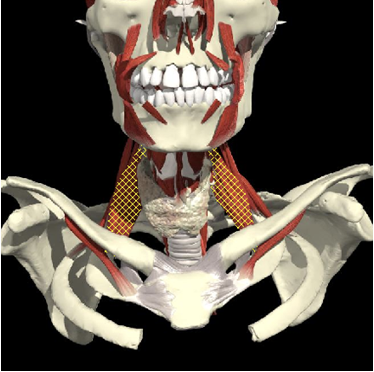

Anterior/Lateral Muscles

Anatomy

Platysma

Scalenus Anterior

SCM

Longus Colli

Cervical Dystonia

- When acting together

- When acting individually

Action

-

- Lateral flexion

- Rotation to the opposite side

- Forward flexion